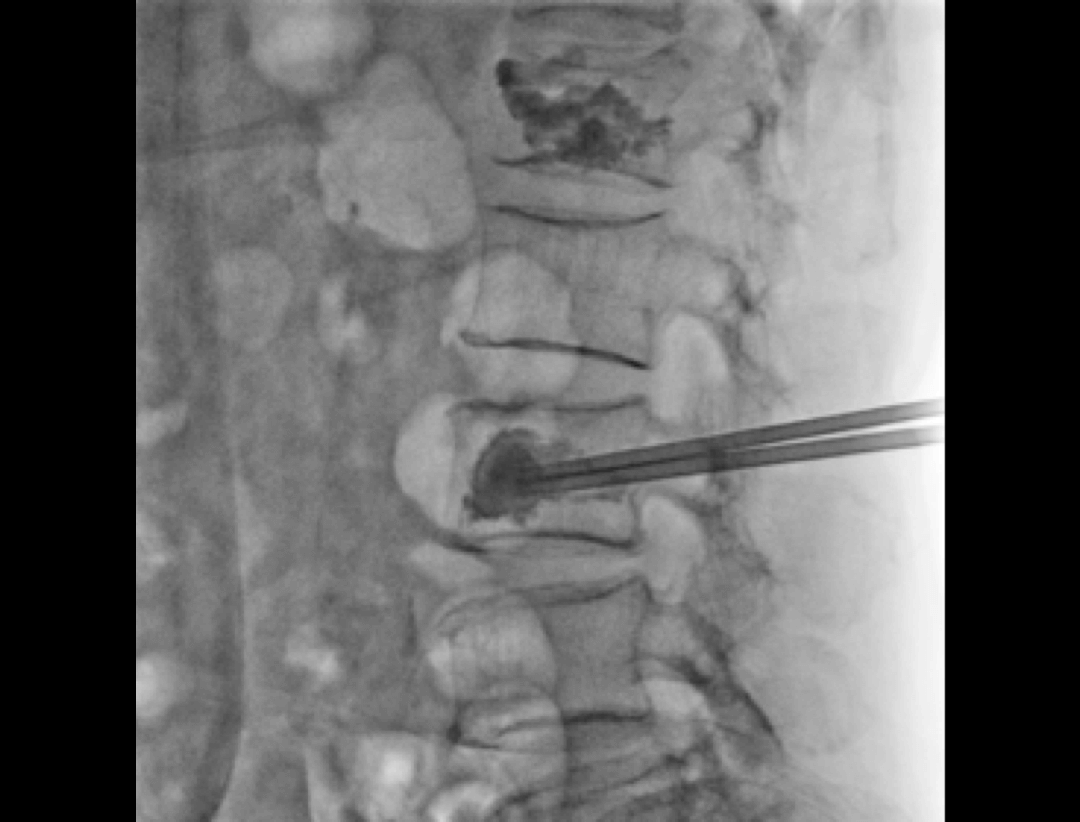

Implantacja śruby przeznasadowej